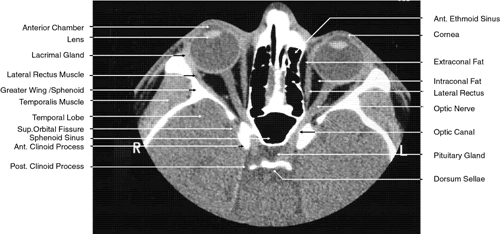

Fig. 28. Axial computed tomography image with contrast medium through cavernous sinus and pituitary gland.

Fig. 29. A. Axial computed tomography soft tissue image at the level of the base of skull. B. Axial computed tomography bone window image at the level of the base of skull.